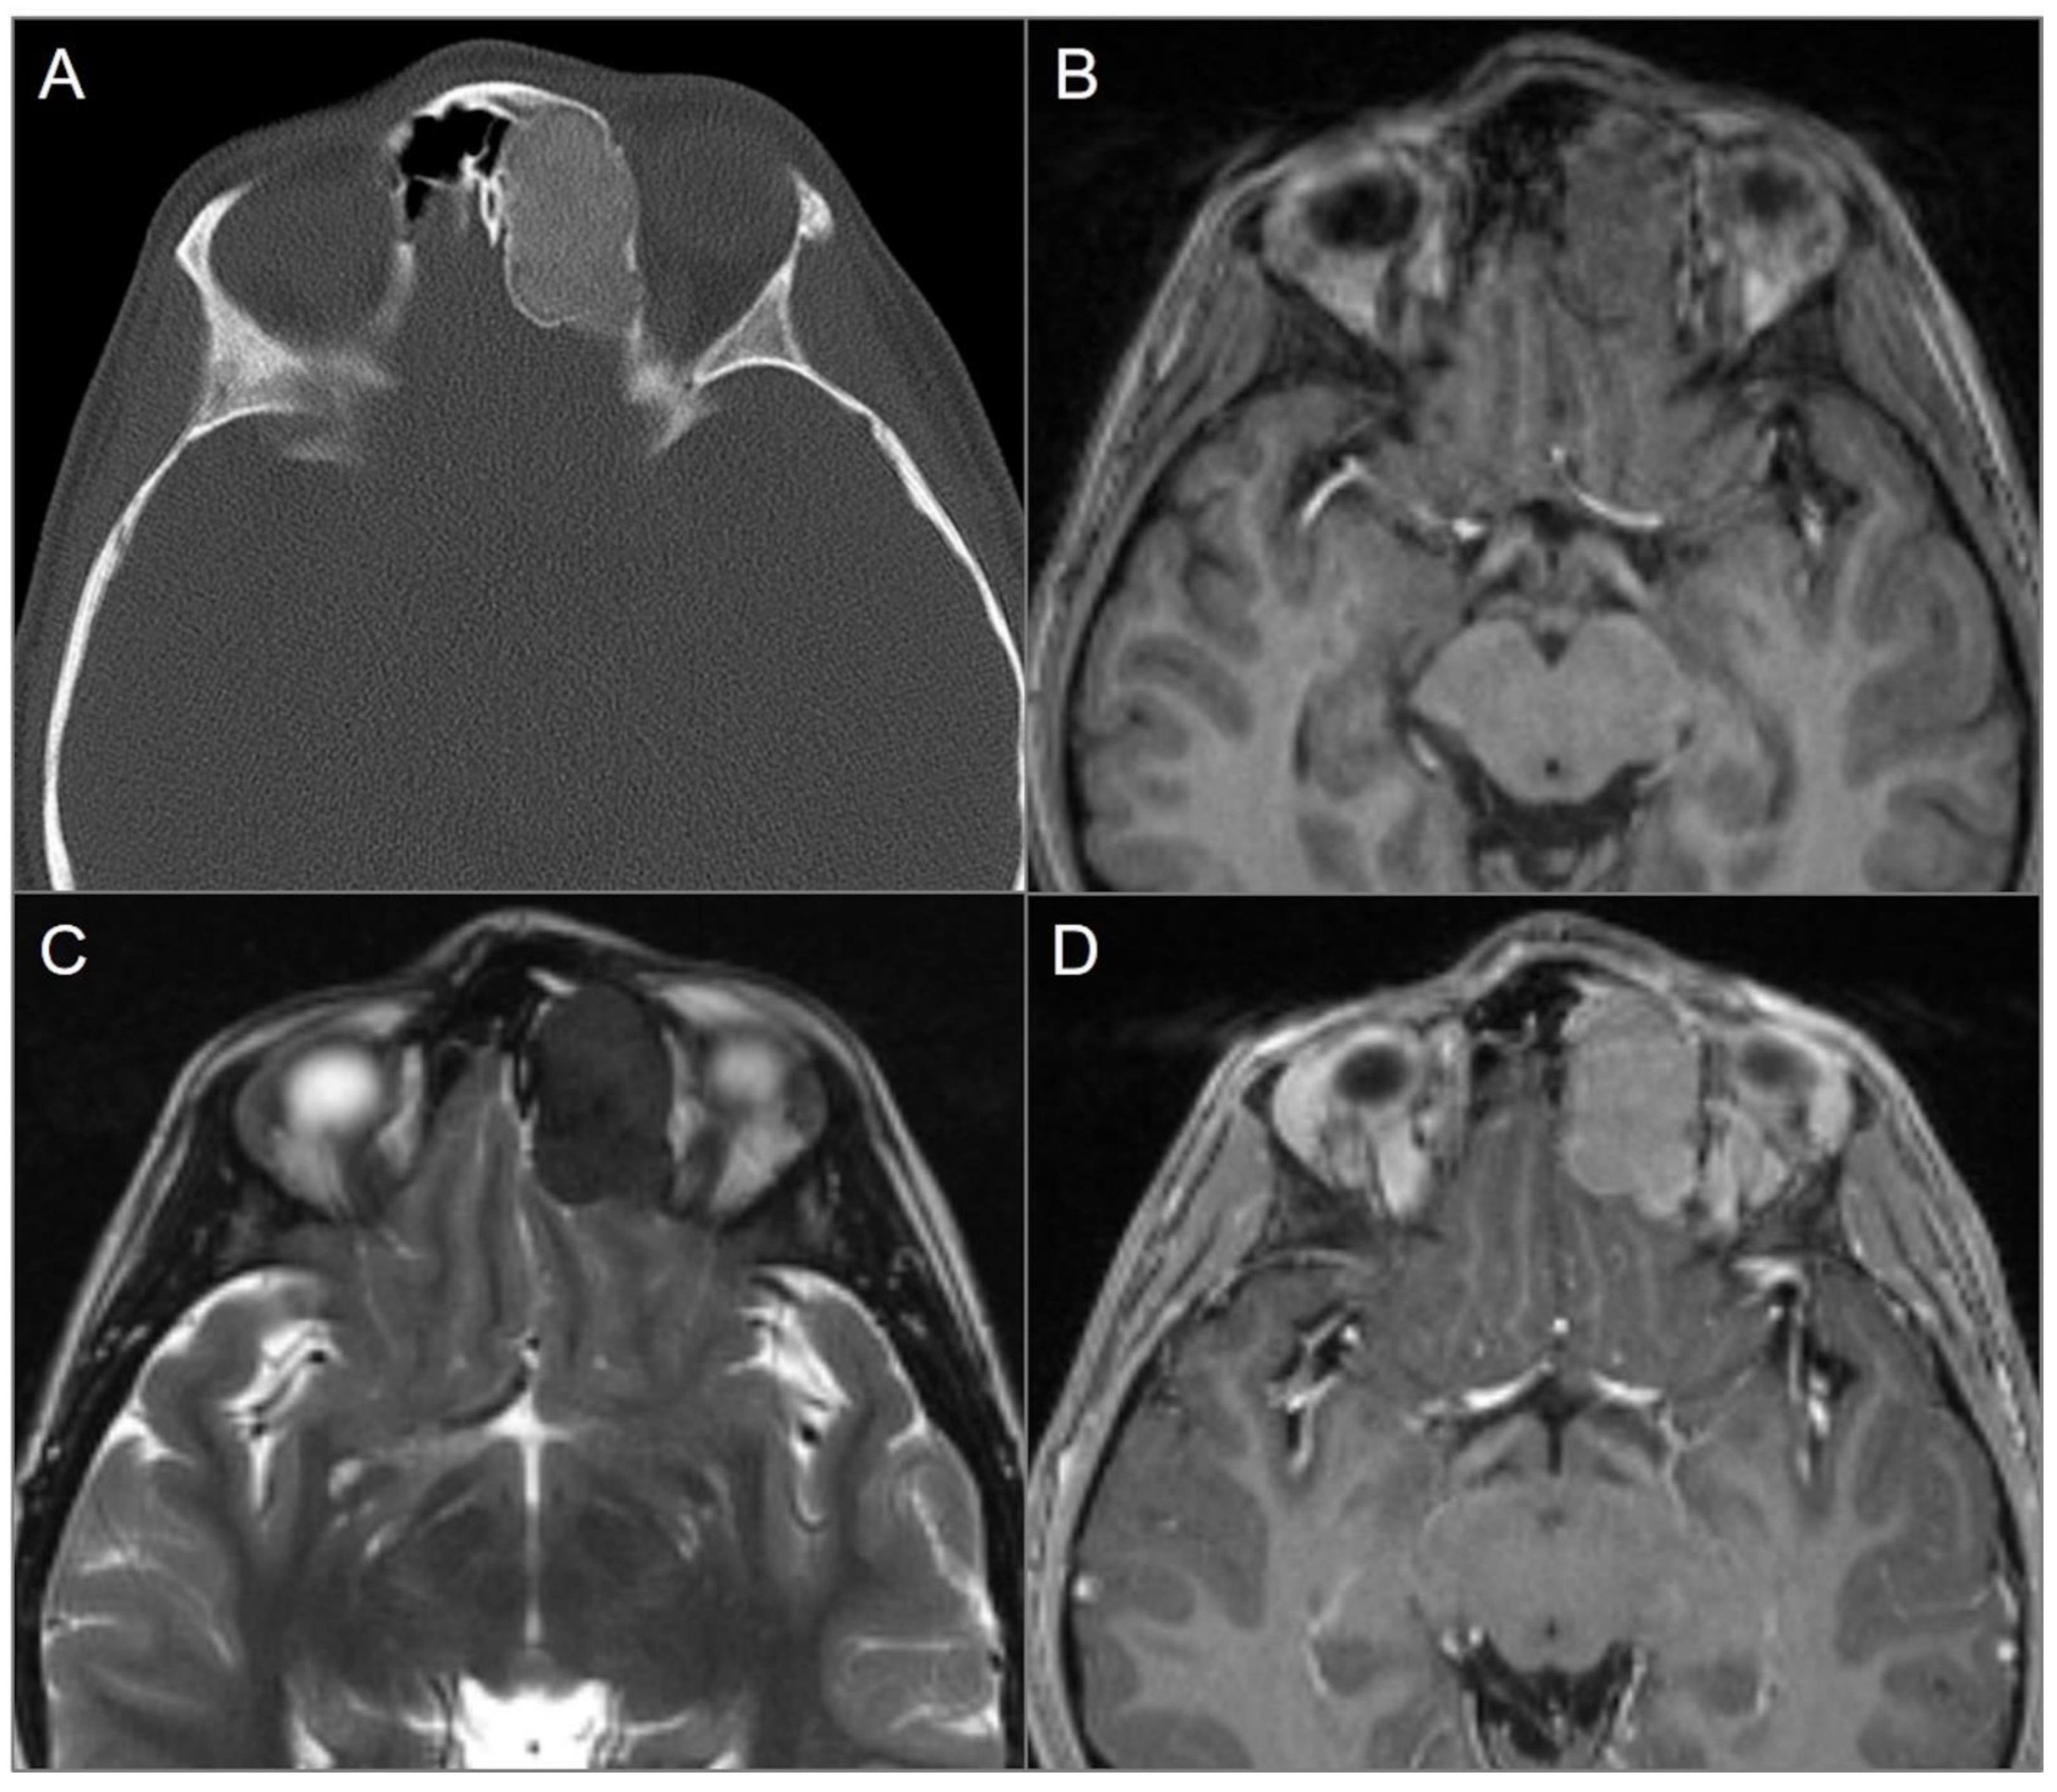

4.4.4. Endolymphatic Sac Tumor